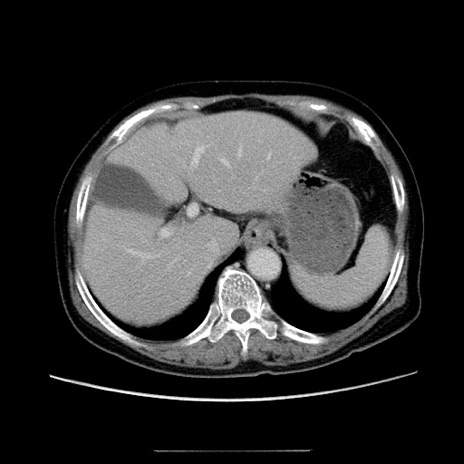

症例5(横断像)

【症例】70歳代女性

【主訴】お腹が張る

【現病歴】1週間くらい前から腹部膨満の自覚あり。昨日夜から増悪したため、本日救急外来受診。

【身体所見】意識清明、BT 36.5℃、BP 165/106mmHg、HR 80bpm、SpO2 98%、腹部:膨満、軟、自発痛・圧痛なし、触診にて不快感あり、腸蠕動音:減弱

【データ】WBC 12600、CRP 1.04